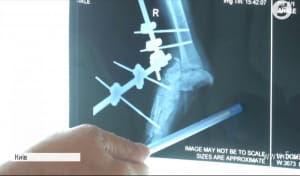

Лікар ортопед-травматолог Володимир Оксимець пояснює: "Петі дуже пощастило. Те, що він не повністю настав на кінцівку, він був на навприсядки. І у нього було хороше взуття… Подивившись перший раз, я розумію, що воно живе і можна боротися за ногу". За спиною лікаря – знімки правої ноги Петра, на яких немає п'яти. Її доведеться відростити, як це зробили, наприклад, іншому пацієнту.

Нову кістку створять з клітин пацієнта. Їх уже взяли і процес росту розпочався. Це інноваційна технологія, яка допомогла вже більш як 40 військовослужбовцям. Проект "Біотех-реабілітація" втілюють волонтери "People's Project".